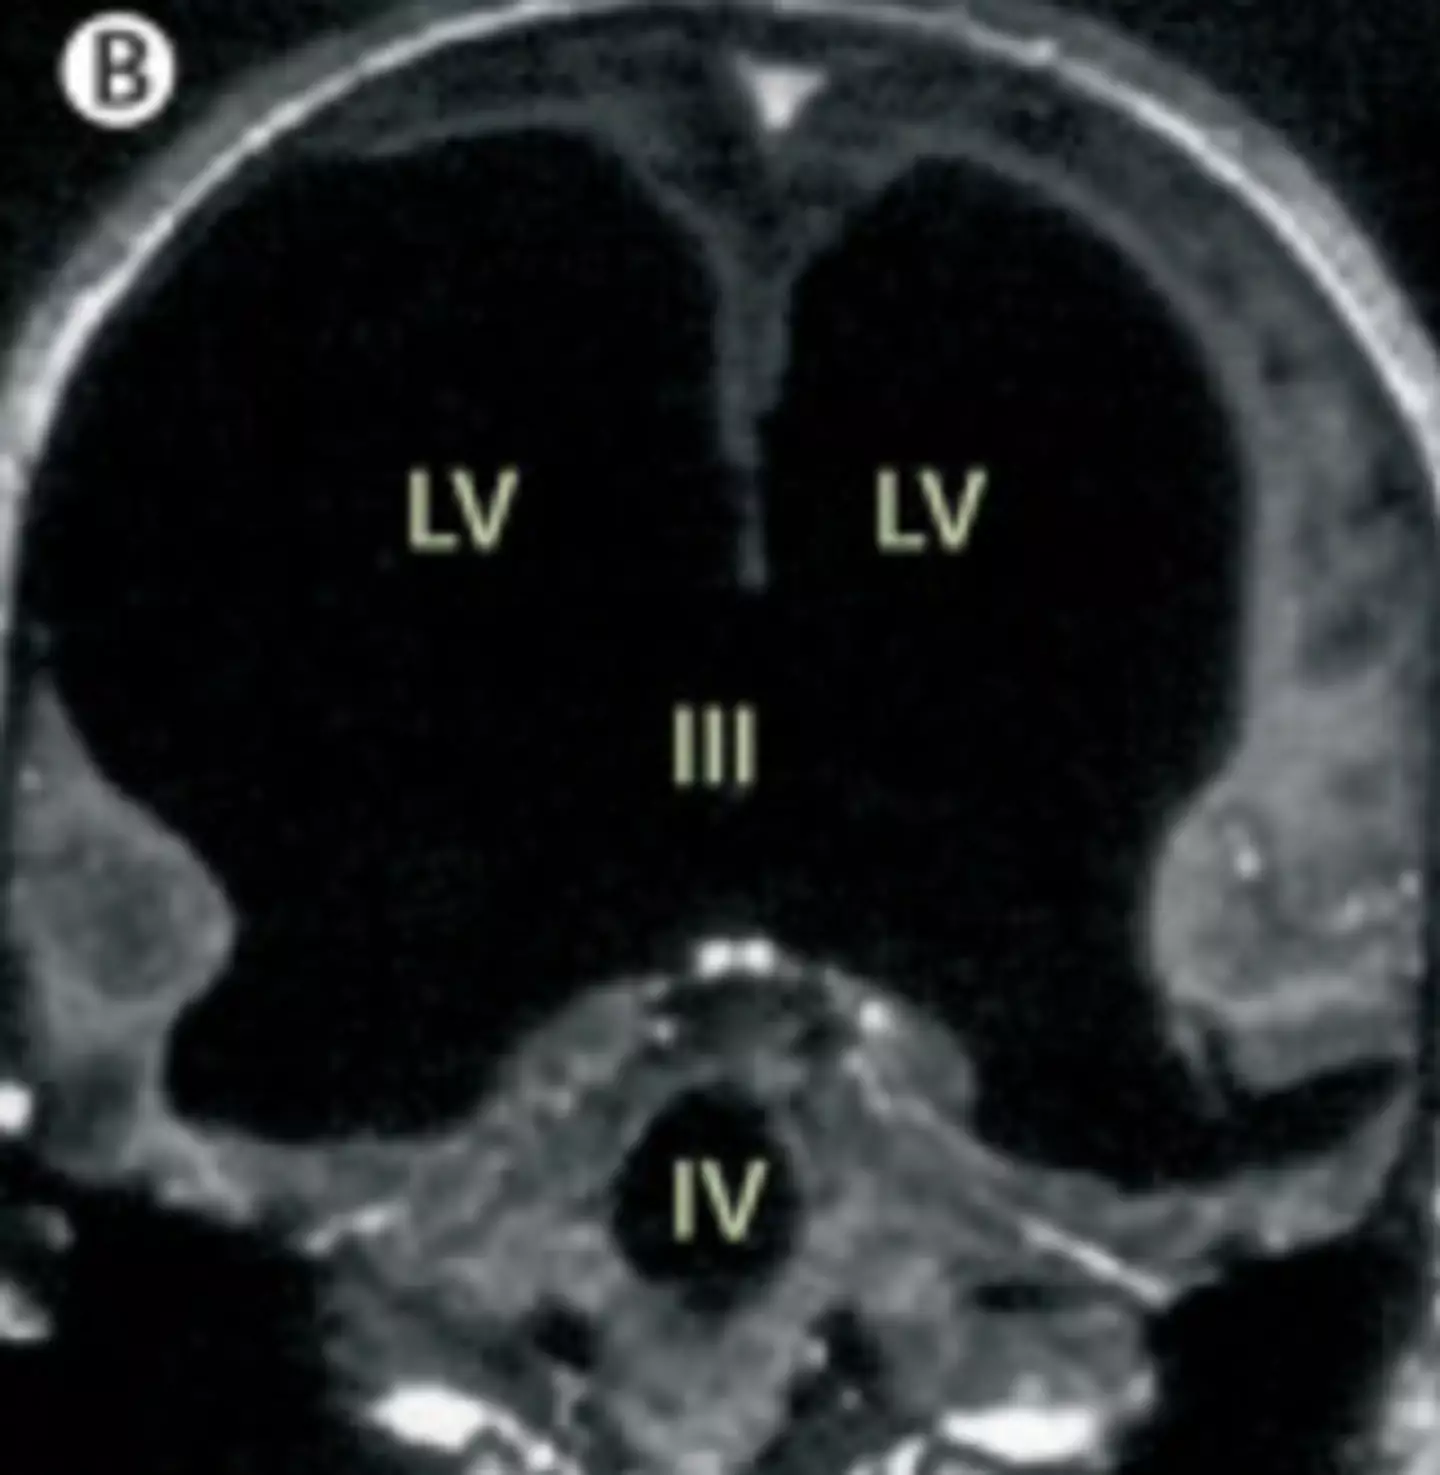

The doctors learned that the man had a condition called Hydrocephalus, a build-up of fluid in the brain; he actually had a shunt placed inside his head at just six years old to drain the fluid, but it was removed when he turned 14.

Speaking about the case, Feuillet confirmed that the fluid buildup had led to a significant reduction in brain matter: "It is hard for me [to say] exactly the percentage of reduction of the brain, since we did not use software to measure its volume. But visually, it is more than a 50 to 75 percent reduction.

"The whole brain was reduced – frontal, parietal, temporal, and occipital lobes – on both left and right sides. These regions control motion, sensibility, language, vision, audition, and emotional and cognitive functions," Feuillet went on to tell New Scientist.